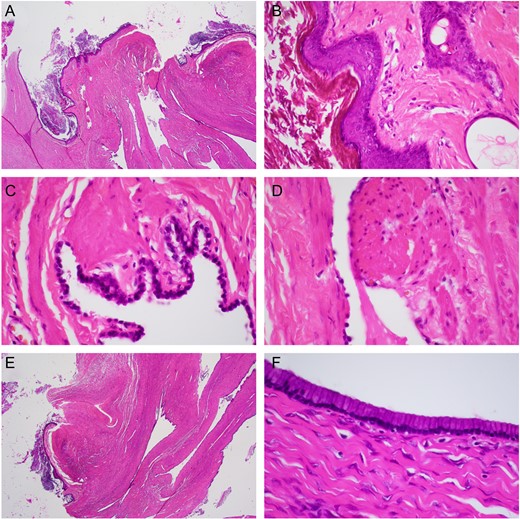

Pathology demonstrated a mucinous cystadenoma with focal proliferation arising in association with a mature cystic teratoma. The two tumors were distinct and no transitional features were recognized histologically. Many of the locules were lined by a single layer of cuboidal to columnar mucinous epithelium with occasional macrophages containing hemosiderin. Focal areas showed proliferation, representing less than 10% of the cyst lining (Fig. 3).

(A) Low power (20×) of mature cystic teratoma lined by ectodermal squamous epithelium (arrowhead), cutaneous appendages, and endodermal glandular/gastrointestinal epithelium. (B) High power (400×) mature cystic teratoma lined by ectodermal squamous epithelium cutaneous appendage (arrowhead). (C) High power (600×) ciliated endodermal respiratory epithelium (arrowhead). (D) High power (600×) endodermal smooth muscle (arrowhead). (E) Low power (20×) mucinous cystic teratoma with adjacent mucinous cystadenoma (arrowhead). (F) High power (400×) mucinous cystadenoma.